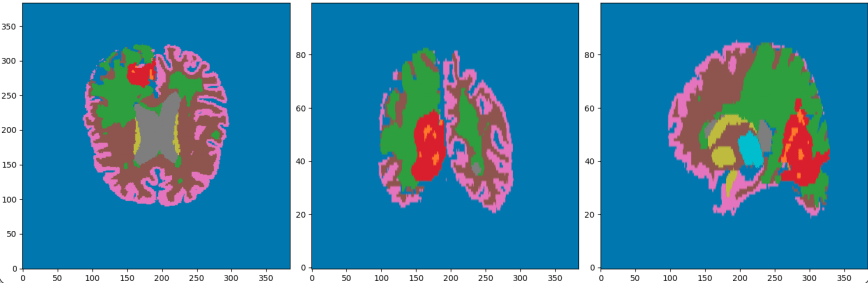

Régions

- WM (substance blanche)

- GM (Substance grise)

- Thalamus

- Ventricules

- Nécrose

- GDE (Rehaussement annulaire)

- Background

États

- Oedème

- Leucopathie

- autres Hyperintensité de T1ce

- Sain